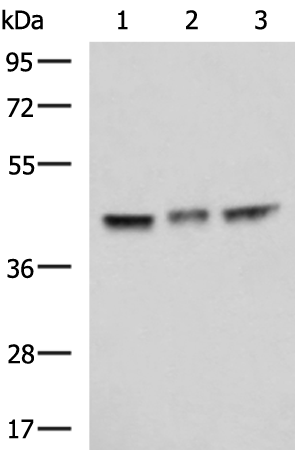

分类: 科研抗体货号: P07391别名: LPS; PIT; PPS; VWS; OFC6; PPS1; VWS1应用: WB,IHC反应种属: Human, Mouse